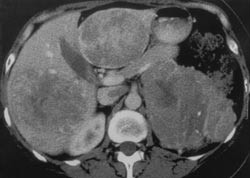

CT-kontroll september 2000 viste ikke tegn til lokalt residiv i buken. Venstre leverlapp hadde regenerert, men gjenværende metastase i høyre leverlapp hadde vokst til en diameter på 12 – 13 cm. Metastasen hadde nær relasjon til høyre portastamme (fig 2). Fordi restleveren venstre side hadde regenerert, fant man det nå riktig å utføre en høyresidig leverreseksjon. Leveren var svært skjør og lettblødende, sannsynligvis på grunn av preoperativ cytostatikabehandling og langvarig steroidpåvirkning. Hun fikk i alt 22 enheter SAG-blod under operasjonen. For øvrig var inngrepet ukomplisert. Etter denne operasjonen var pasienten makroskopisk fri for tumorvev. Hun var postoperativt betydelig slapp og trett den første uken, men kom seg deretter raskt. Hennes hormonverdier normaliserte seg, og hun fikk igjen menstruasjonen. Pasienten har fått kortisonmedikasjon etter den siste operasjonen da mitotan hemmer egenproduksjonen av binyrebarkhormoner.